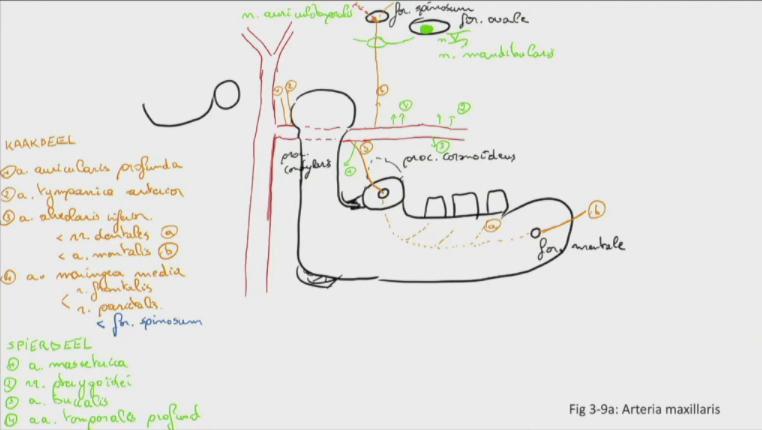

Fig 3.09a: a. maxillaris - takken van het kaakdeel en spierig deel

A kaakdeel (oranje)

(a auricularis profunda) (a tympanica anterior) -

a alveolaris inferior

-

a meningea media

B spierig deel (groen)